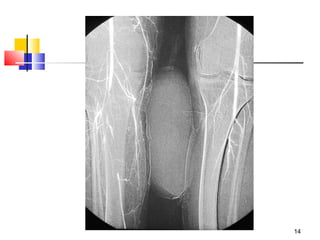

Investigations

 Doppler examination – bed side

 Angiography – only if time permits

 Others – of limited value